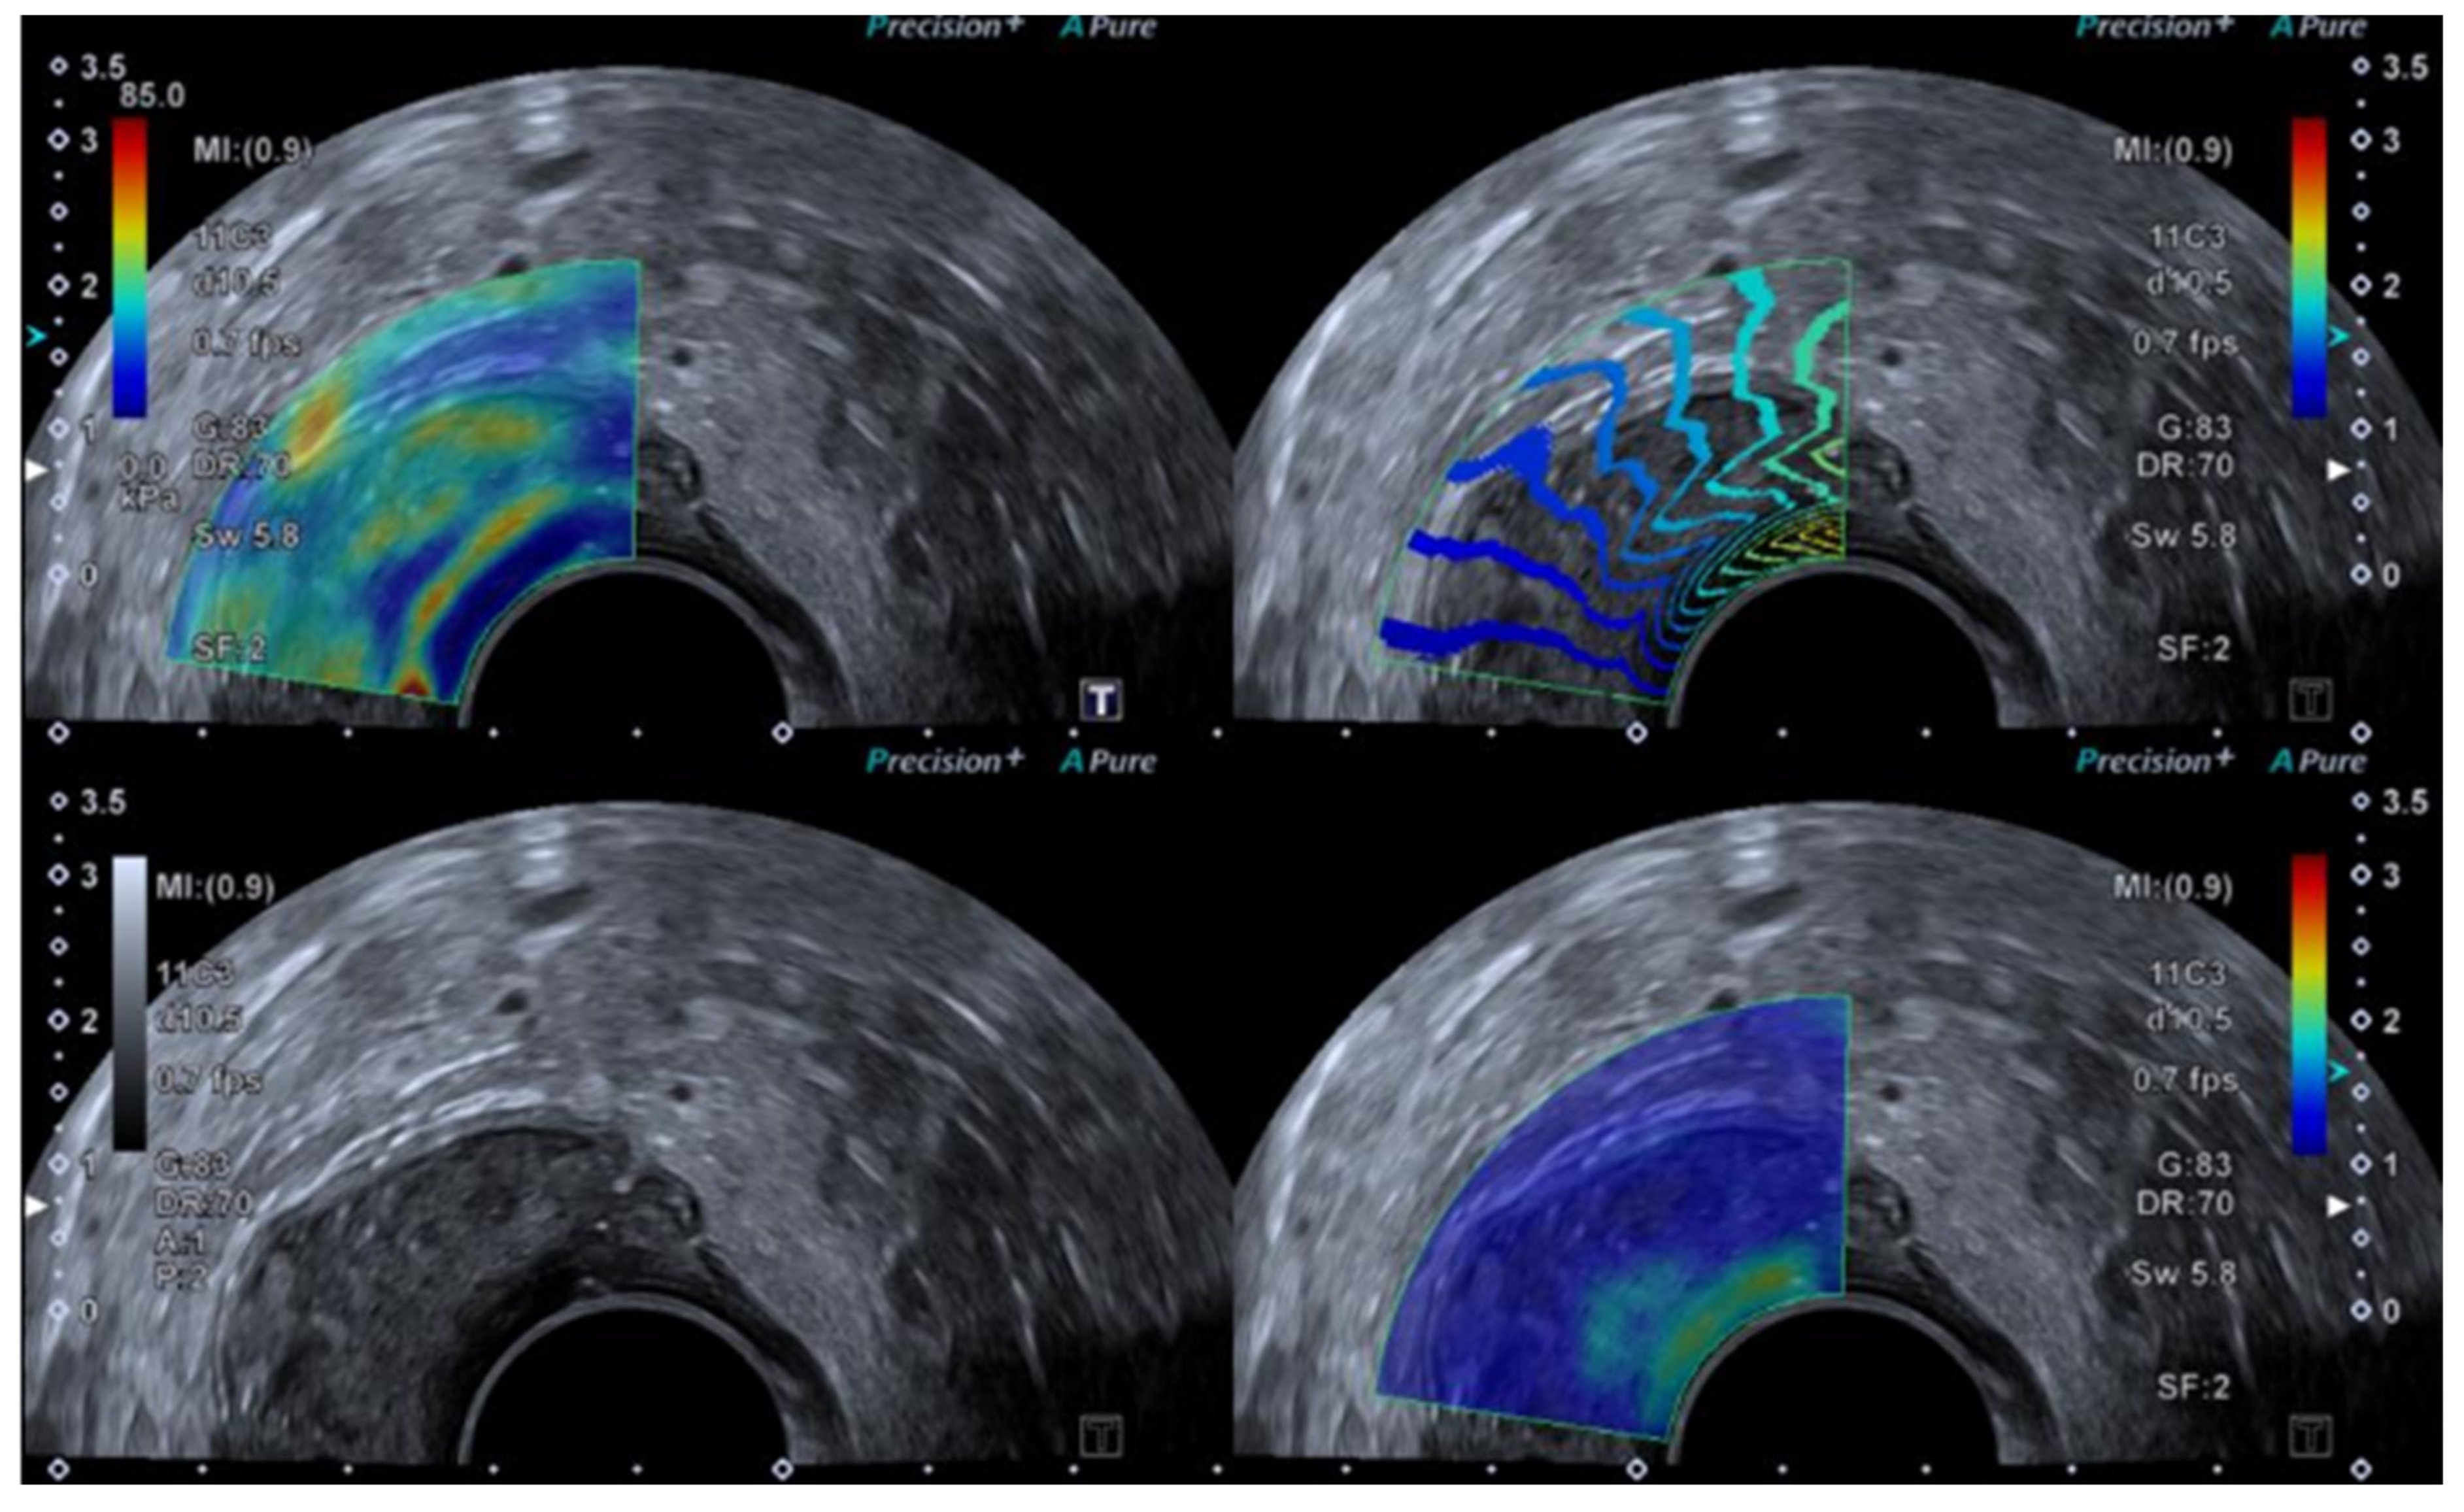

Figure 3.

SWE ultrasound showing a polyp in an 85-year-old female.

SWE uses a push pulse to induce shear waves, and an elastogram is created by monitoring shear wave speed through the tissue. The transducer is held still, without applying pressure to the tumour area, for approximately 5–10 s until a satisfying elastogram is created on the monitor. A region of interest (ROI) may be placed covering the entire lesion or placed within the stiffest areas of the tumour. The elastography index is reported as either the mean or the maximal value of the ROI. SWE may also be interpreted using a visual colour scale [29,30,31,32].

Several cut-off values have been suggested for both SE and SWE (see Table 1); however, it is important to keep in mind that the elastography value differs depending on the technical approach, equipment, and software used, as well as intra- and inter-variation between operators.